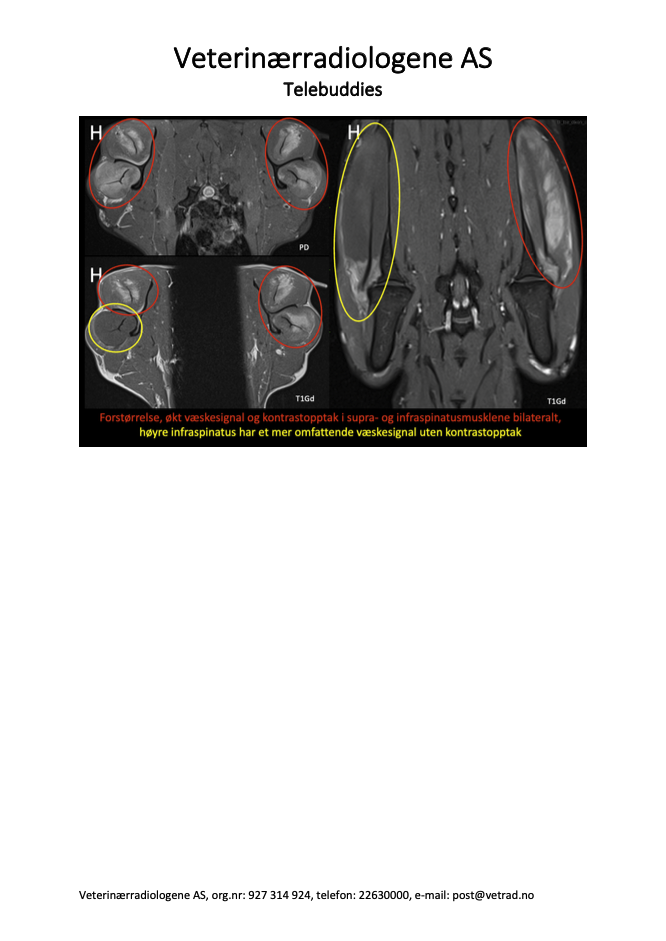

Endelig er vi i gang med kasus igjen, og vi starter høstsesongen med denne godbiten som ble sendt inn til oss fra AniCura Jeløy Dyresykehus. Ha gjerne denne i bakhodet hvis det kommer inn jakthunder eller andre veldig aktive hunder med halthet fra skulder i høst! Signalement: Engelsk setter, Hannhund, 3 år Anamnese: Akutt halt høyre frambein etter jakt Kliniske funn: 4-5/5 grader halt høyre frambein, smerte ved fleksjon av skulder. Ikke medial instabilitet. Mediolaterale og craniocaudale røntgenbilder av begge skuldre er uten unormale funn.